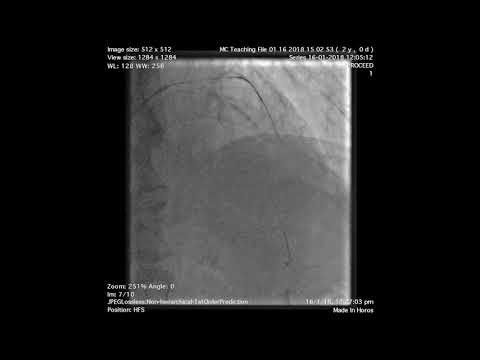

Imaging Guided High Risk of LM Trifurcation LAD and LCx - Complex Coronary Cases - February 19, 2019

(20 min CCC Feb '19) Imaging Guided High Risk of LM Trifurcation LAD and LCx